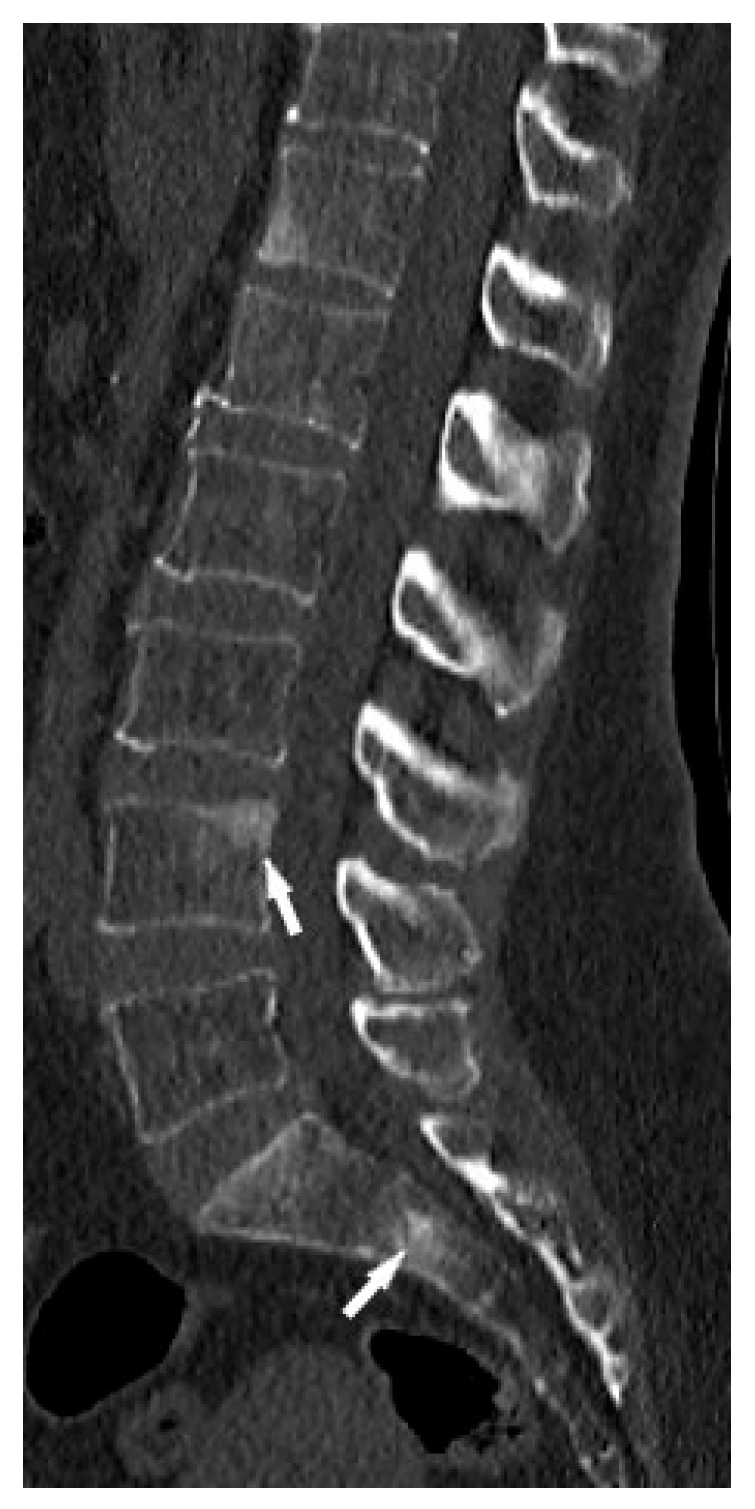

CT is superior to X-ray in detecting bone lesions and could provide valuable information for treatment planning. The CT images categorize the bone lesions as osteolytic, osteosclerotic or mixed lytic-sclerotic (Figure 2). Evaluation of foci in the long bones and axial skeleton does not require the administration of iodine contrast agent; three-plane evaluation of bone window lesions is sufficient.

In the long bones and axial skeleton, bone lesions can have an osteolytic, osteosclerotic or mixed appearance. Osteosclerotic lesions are more common in the spine [19]. Unlike phalanges, they do not cause disruption of the cortex or involvement of the surrounding soft tissues.

Figure 2. Lumbar spine CT, bone window. Osteosclerotic lesions (white arrows) in the L3 and S2 vertebral bodies.